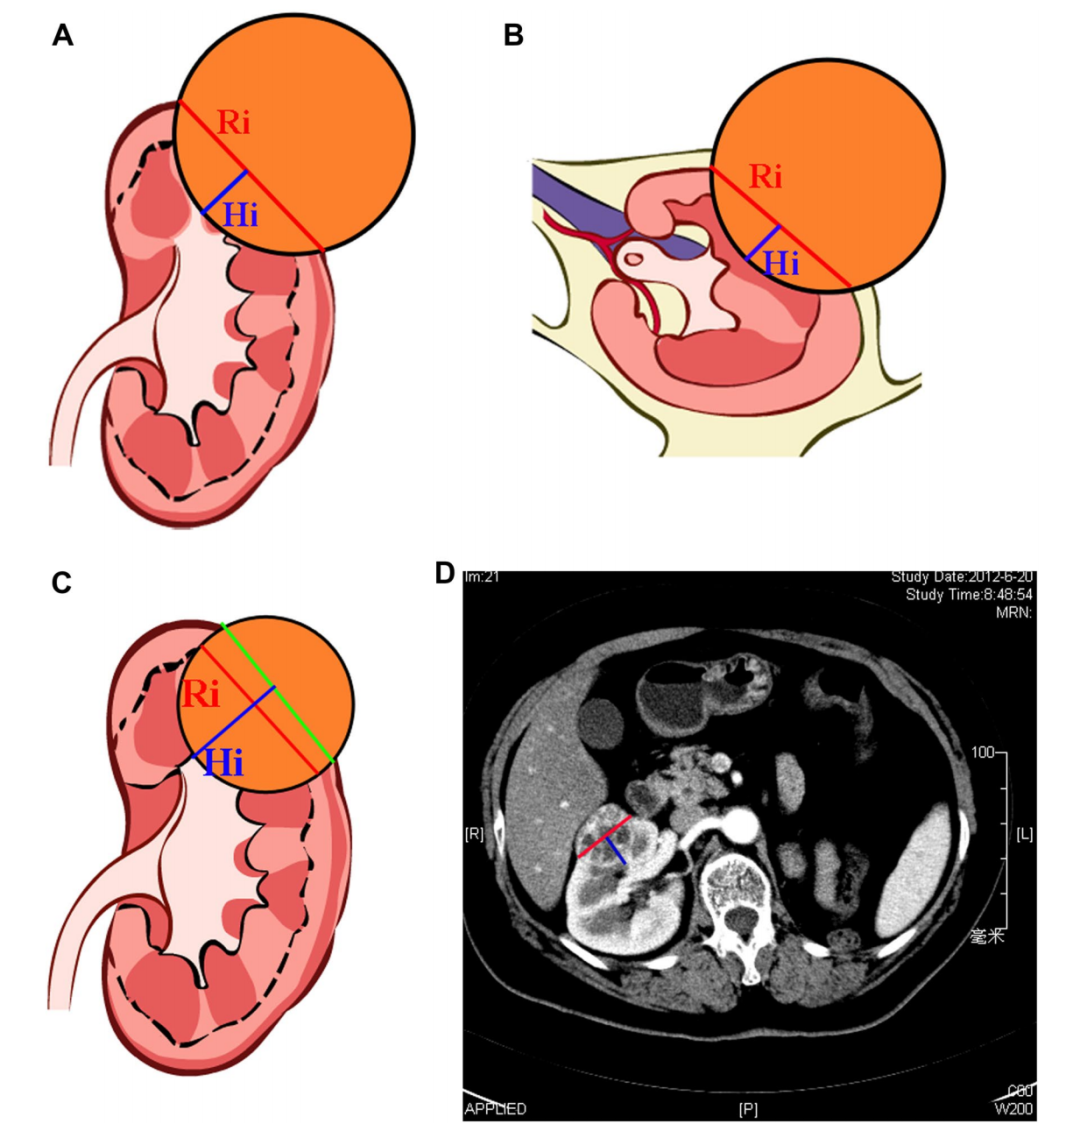

鉴于此,我们团队通过学习相关经验,基于庞大的肾癌数据库以及多年的手术经验,提出了中山评分系统的方案。该评分系统以肾内最大肿瘤直径(Ri)为评价核心,并评估肿瘤位置(Loation)和肿瘤深度(Depth)等指标。评分越低代表手术时间短,出血量少,并发症少,复发率低,避免了国外比较粗浅的分类方式,证明了我们的评分系统的科学性,得到了国际上的广泛认可。

肾癌手术的中山评分系统ZS Score(Medicine. 2015)

中山评分系统是我国自主研发的评分系统,还是比较引人注目的;但外国人习惯使用以往的评分标准,所以在国际上推广起来比较困难。然而,我们的评分系统非常科学,是以肾脏内最大肿瘤直径为主要依据,肿瘤直径用CT测量即可,美国的研究人员也进行了类似的评分系统研究,但其研究是以肿瘤覆盖肾内的面积为依据,需要经过复杂的计算,因此实用性较差。